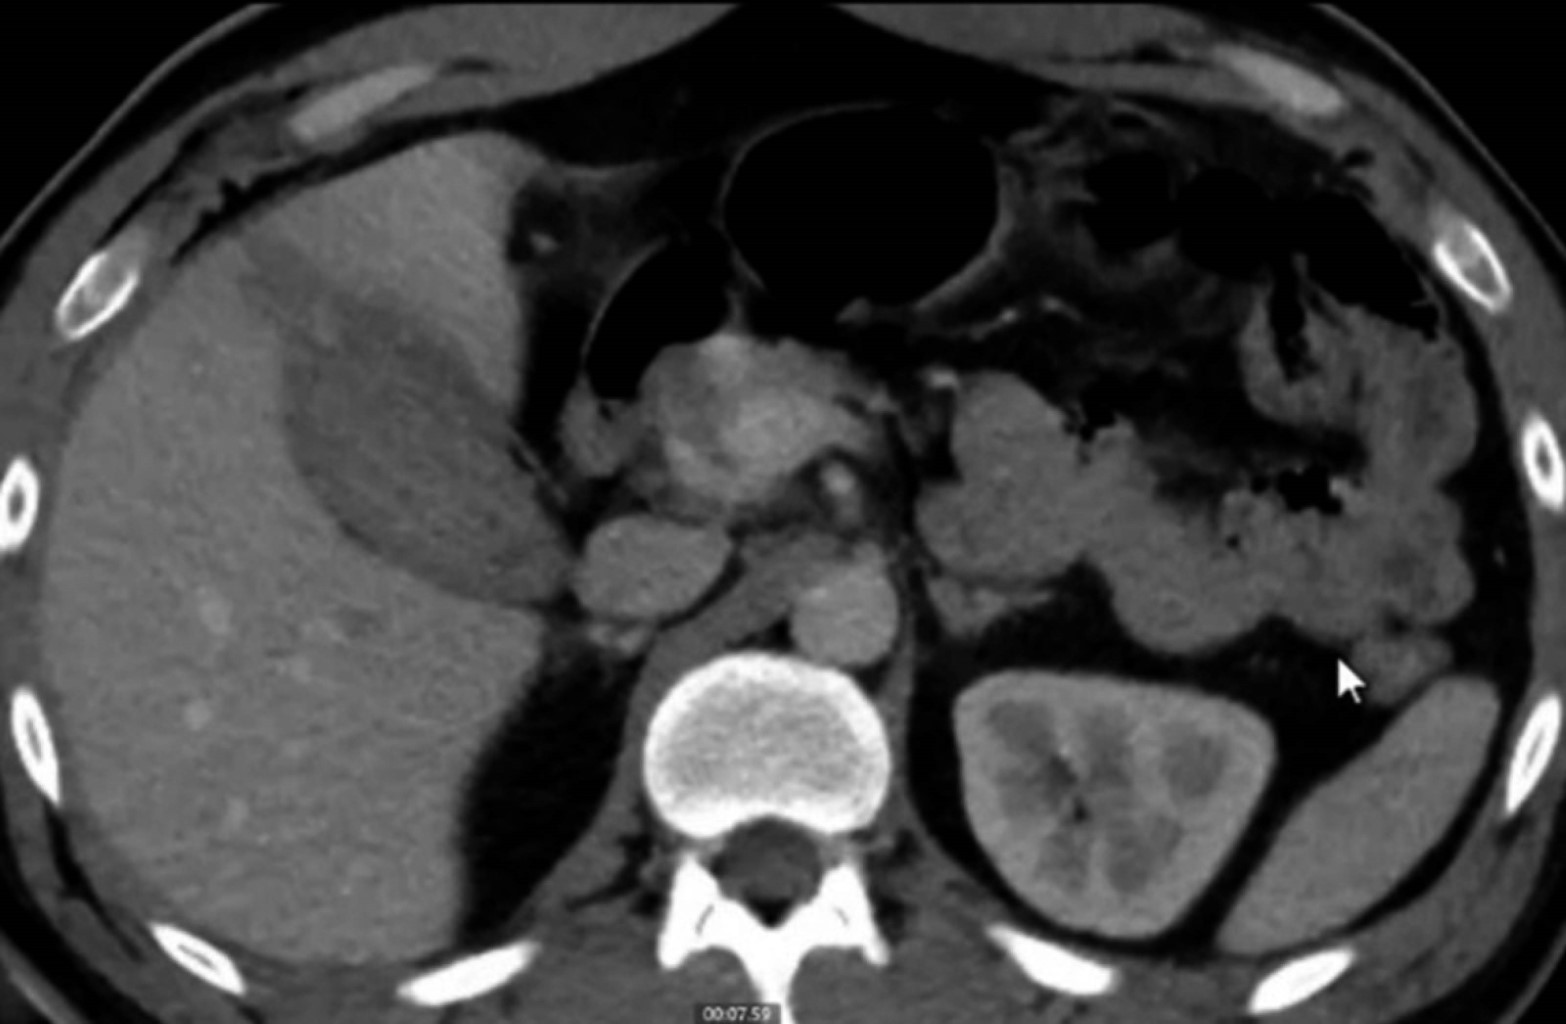

El paciente continúa sin datos de irritación peritoneal, sin abdomen agudo, aunque por datos de probable hemobilia, se solicita tomografía computarizada (TC) de abdomen a las 29 horas de evolución reportando: laceración hepática del segmento V grado I de la AAST, vesícula de 81 × 44 × 48 mm de contenido heterogéneo, descrita en la Figura 3.

Un signo patognomónico de perforación es la extravasación del contraste intraluminal a través de la lesión asociada a líquido perihepático.1 Por lo que, al tener un paciente estable sin datos de choque, sin ameritar manejo urgente quirúrgico, se solicitó una tomografía de abdomen, reportando probable contenido hemático en vesícula biliar, sin datos de solución de continuidad en la pared vesicular.